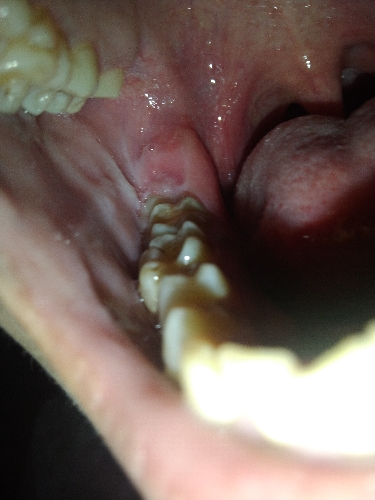

Em bị Sưng nú răng đâu nhức khó chịu bác sĩ có cách nào điều trị hết tại nhà không ạ ?

Sưng sau răng cuối cùng a ơi mới bị hôm nay nuốt nước bọt cũng đau

Răng cuối cùng a à